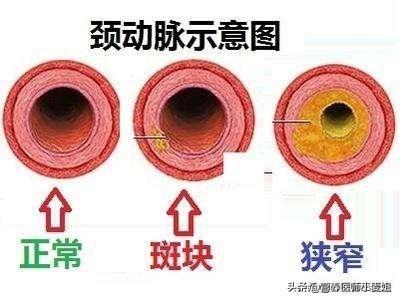

- a. 動脈硬化:これが最も一般的な原因である。脳につながる動脈の開存性と脳内の動脈の開存性の両方に影響を及ぼす。頸動脈は脳に血液を供給する最も重要な動脈のひとつである。アテローム性動脈硬化症は頸動脈にプラークを形成する。アテローム性動脈硬化症は頸動脈にプラークの形成をもたらし、プラークの形成は血管の内腔の狭窄をもたらし、内腔の狭窄は脳への血流不足をもたらす。

動脈硬化は全身の動脈に影響を及ぼすが、脳内の動脈は免れない。その結果、脳への血流が悪くなり、脳内の血流も悪くなる。二重の影響が脳への血液供給に影響し、脳への血液供給が不足する。動脈硬化は高齢者の血液供給不足の最も重要な原因である。

血管が原因。血管壁の損傷、内腔の狭窄、血管攣縮などである。脳動脈硬化、壁に硬化したプラークの形成、内腔の狭小化、菲薄化、血管抵抗の増大による血流量の減少、特に脳を長時間にわたって酷使し続けた後に、脳血液の供給と相対的に起こることが多い。

頸動脈などのプラークは、血流が通過するにつれて小さくなるため、脳への血液供給不足につながる。この病変は超音波検査で発見することができ、一般的な治療方針は、血圧をコントロールし、血中脂質を下げることで、プラークが大きくなるのを防ぎ、腫瘍性プラークを予防することを目指すが、プラークを除去することはできない。プラークがあまりに大きく、脳への血液供給に深刻な影響を及ぼすような場合には、外科的切除も選択肢となる。